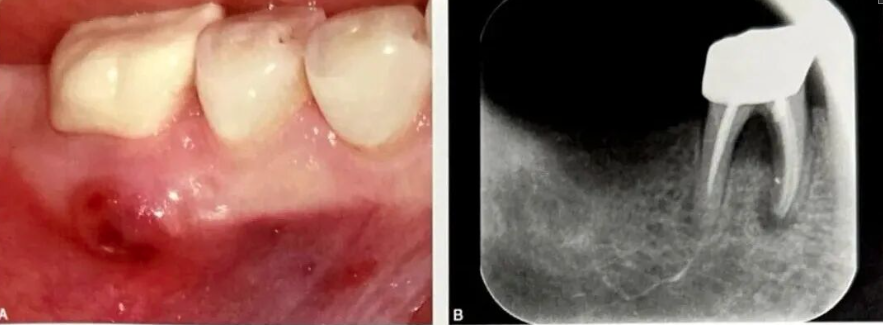

图2: 口腔检查显示患者存在侧切牙区域的露龈笑,我们告知她需要进行双侧手术治疗以改善美观。